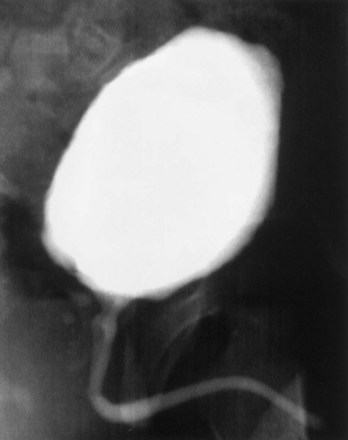

The bladder submucosa matrix (Chen et al, 1999), proved to be a suitable graft for repair of urethral defects in rabbits. The neourethras demonstrated a normal urothelial luminal lining and organized muscle bundles. These results were confirmed clinically in a series of patients with a history of failed hypospadias reconstruction wherein the urethral defects were repaired with human bladder acellular collagen matrices (Atala et al, 1999). The neourethras were created by anastomosing the matrix in an onlay fashion to the urethral plate. The size of the created neourethra ranged from 5 to 15 cm. After a 3-year follow-up, three of the four patients had a successful outcome in regard to cosmetic appearance and function (Fig. 19–5). One patient who had a 15-cm neourethra created developed a subglanular fistula. The acellular collagen-based matrix eliminated the necessity of performing additional surgical procedures for graft harvesting, and both operative time and the potential morbidity from the harvest procedure were decreased. Similar results were obtained in pediatric and adult patients with primary urethral stricture disease using the same collagen matrices (El-Kassaby et al, 2003). Another study in 30 patients with recurrent stricture disease showed that a healthy urethral bed (two or fewer prior urethral surgeries) was needed for successful urethral reconstruction using the acellular collage-based grafts (El Kassaby et al, 2008). More than 200 pediatric and adult patients with urethral disease have been successfully treated in an onlay manner with a bladder-derived collagen-based matrix. One of its advantages over nongenital tissue grafts used for urethroplasty is that the material is “off the shelf.” This eliminates the necessity of additional surgical procedures for graft harvesting, which may decrease operative time as well as the potential morbidity due to the harvest procedure.

Figure 19–5 Urethrogram 6 months after surgery in a patient who had a portion of his urethra replaced with the use of regenerative medicine techniques.